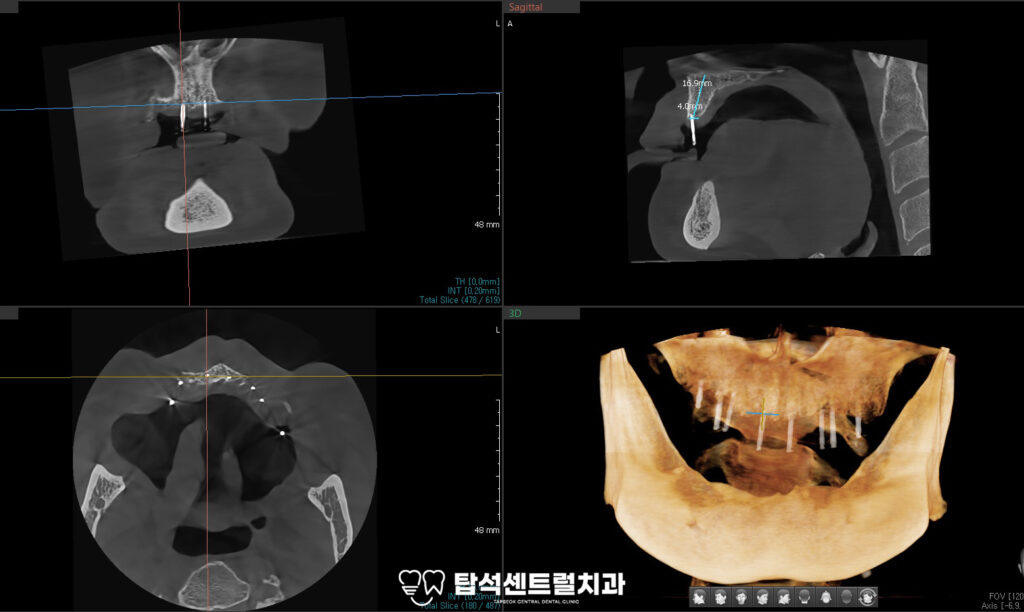

이때 IBS magic guide pin을 활용하면

임플란트의 식립 위치를 정확히 할 수 있으며.

이를 기반으로 수술이 이루어지기 때문에

보다 안전하고 안정적인 결과를

기대해 볼 수 있습니다.

가이드핀을 이용해 임플란트 식립 위치를

정확히 확인할 수 있기 때문에

상악과 마찬가지로 하악 또한

가이드핀을 활용하여

정확한 위치와 각도를 확인합니다.